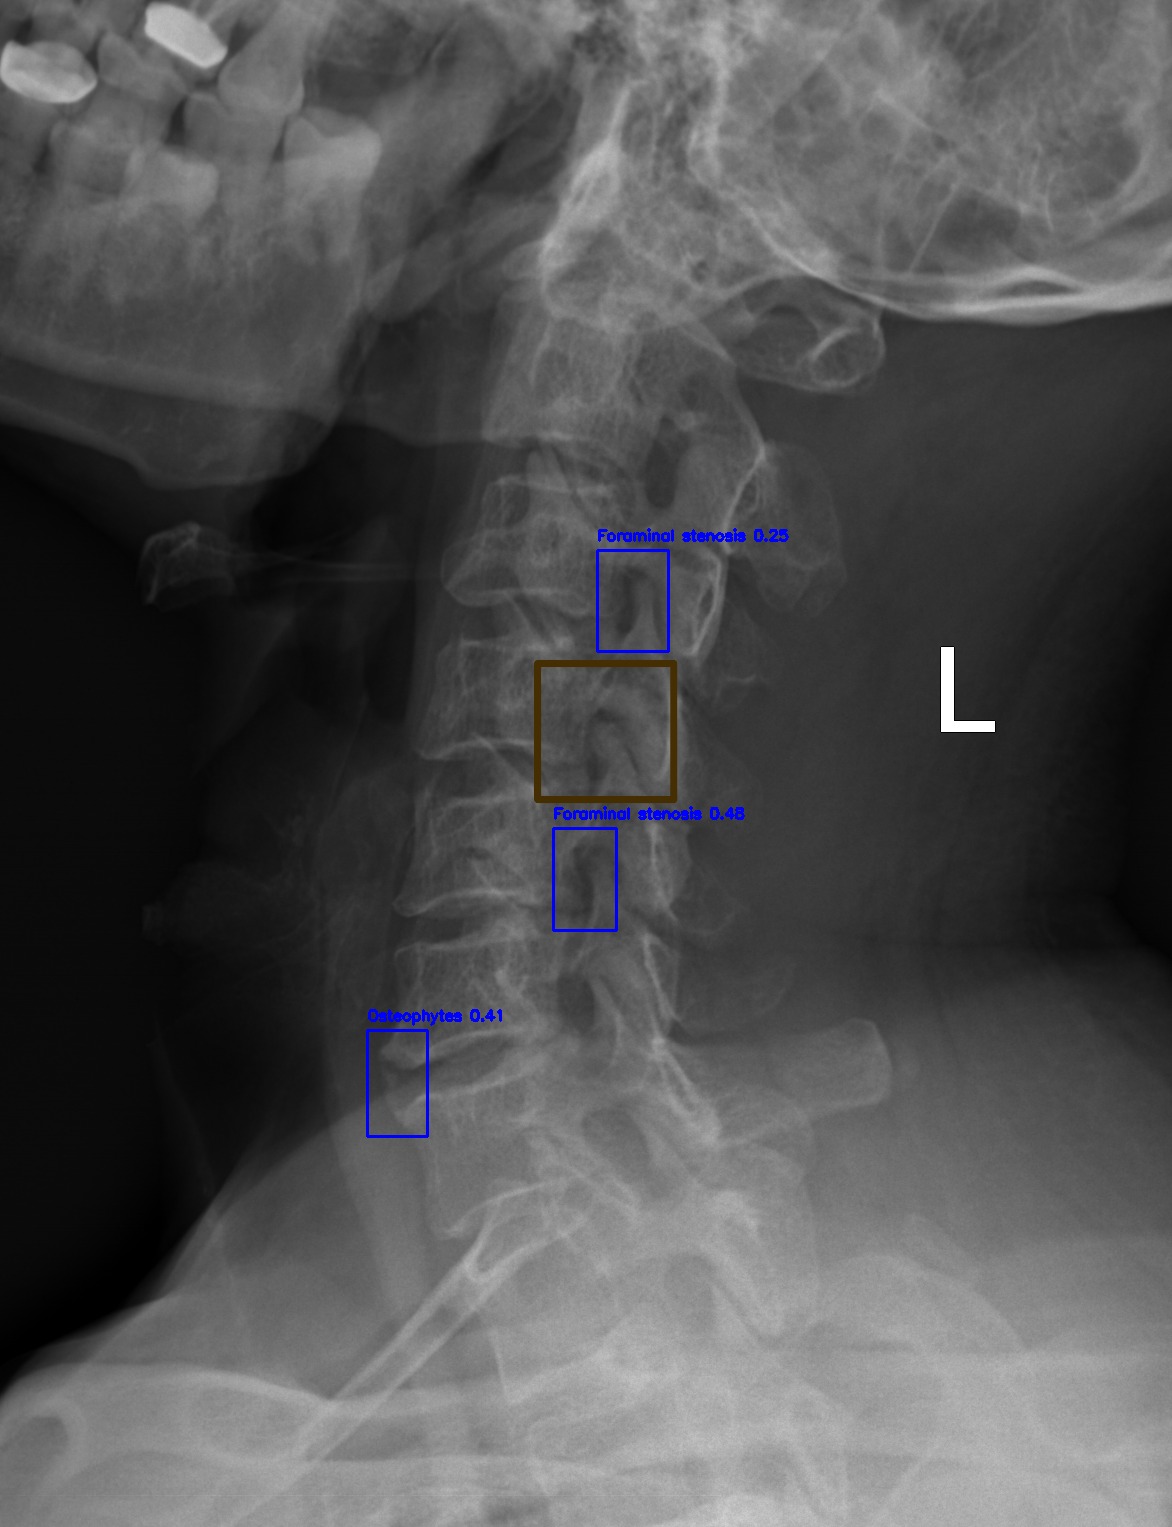

Automated Lesion Detection and Localization: Visual demonstration of the cascaded DERNet-YOLO11 framework on VinDr-SpineXR benchmark images. The figure presents eight representative cases including seven pathological conditions with precise bounding-box localization: (a) Vertebral Collapse, (b) Osteophytes, (c) Spondylolisthesis, (d) Surgical Implants, (e) Disc Space Narrowing, (f) Foraminal Stenosis, (g) Other Lesions, alongside (h) a Normal spine radiograph for comparison. Each pathological case demonstrates the model's capability to accurately detect and spatially localize subtle lesions despite significant class imbalance (46.9:1 ratio), small object scales (often <1% of image area), and anatomical structure overlap. The localization boxes validate the clinical applicability of the integrated triage–localization pipeline.

Foraminal Stenosis

(f) Foraminal Stenosis